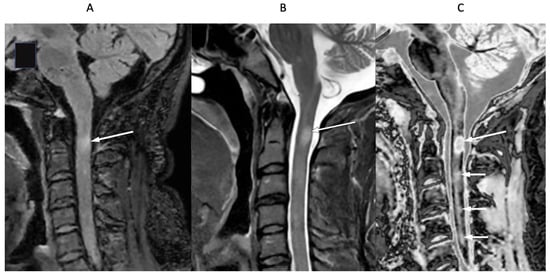

Figure 15 shows T2-FLAIR (Figure 15A) and wide mD dSIR (Figure 15B) sagittal images of the upper cervical spinal cord in a 43-year-old female patient with MS in remission. The T2-FLAIR image shows a poorly defined smudge of increased signal (white arrow). In the corresponding position, the dSIR image (Figure 15B) shows a high-contrast lesion with sharply defined boundaries, which is much more extensive than in (Figure 15A) (lower three arrows). An additional lesion is seen in the medulla on the dSIR image (highest arrow), but is not seen on the T2-FLAIR image.

Figure 15.

Forty-three-year-old female patient with MS in remission. Sagittal 3D T2-FLAIR (A) and 3D wide mD dSIR (B) images. The T2-FLAIR image shows a poorly defined area of increased signal in the cervical cord (arrow). The dSIR image shows a high contrast lesion with sharply defined boundaries, which is much more extensive than in (A) (lower three arrows). An additional lesion is seen in the medulla on the dSIR image (highest arrow) (B), but not on the T2-FLAIR image.

Figure 16 shows the upper cervical spinal cord in a 42-year-old female patient with MS in remission. T2-FLAIR (Figure 16A), T2-wSE (Figure 16B), and wide mD dSIR (Figure 16C) images are compared. A large lesion is seen on all three images, but with greatest contrast on the dSIR image (long white arrows). In addition, three small lesions are only seen on the dSIR image (Figure 16C, short white arrows).

Figure 16.

Forty-two-year-old female patient with MS in remission. Sagittal T2-FLAIR (A), T2-wSE (B), and wide mD dSIR (C) images. A large lesion is seen on all three images but with higher contrast on the dSIR image (long arrows). Three small lesions are only seen on the dSIR image (short arrows).